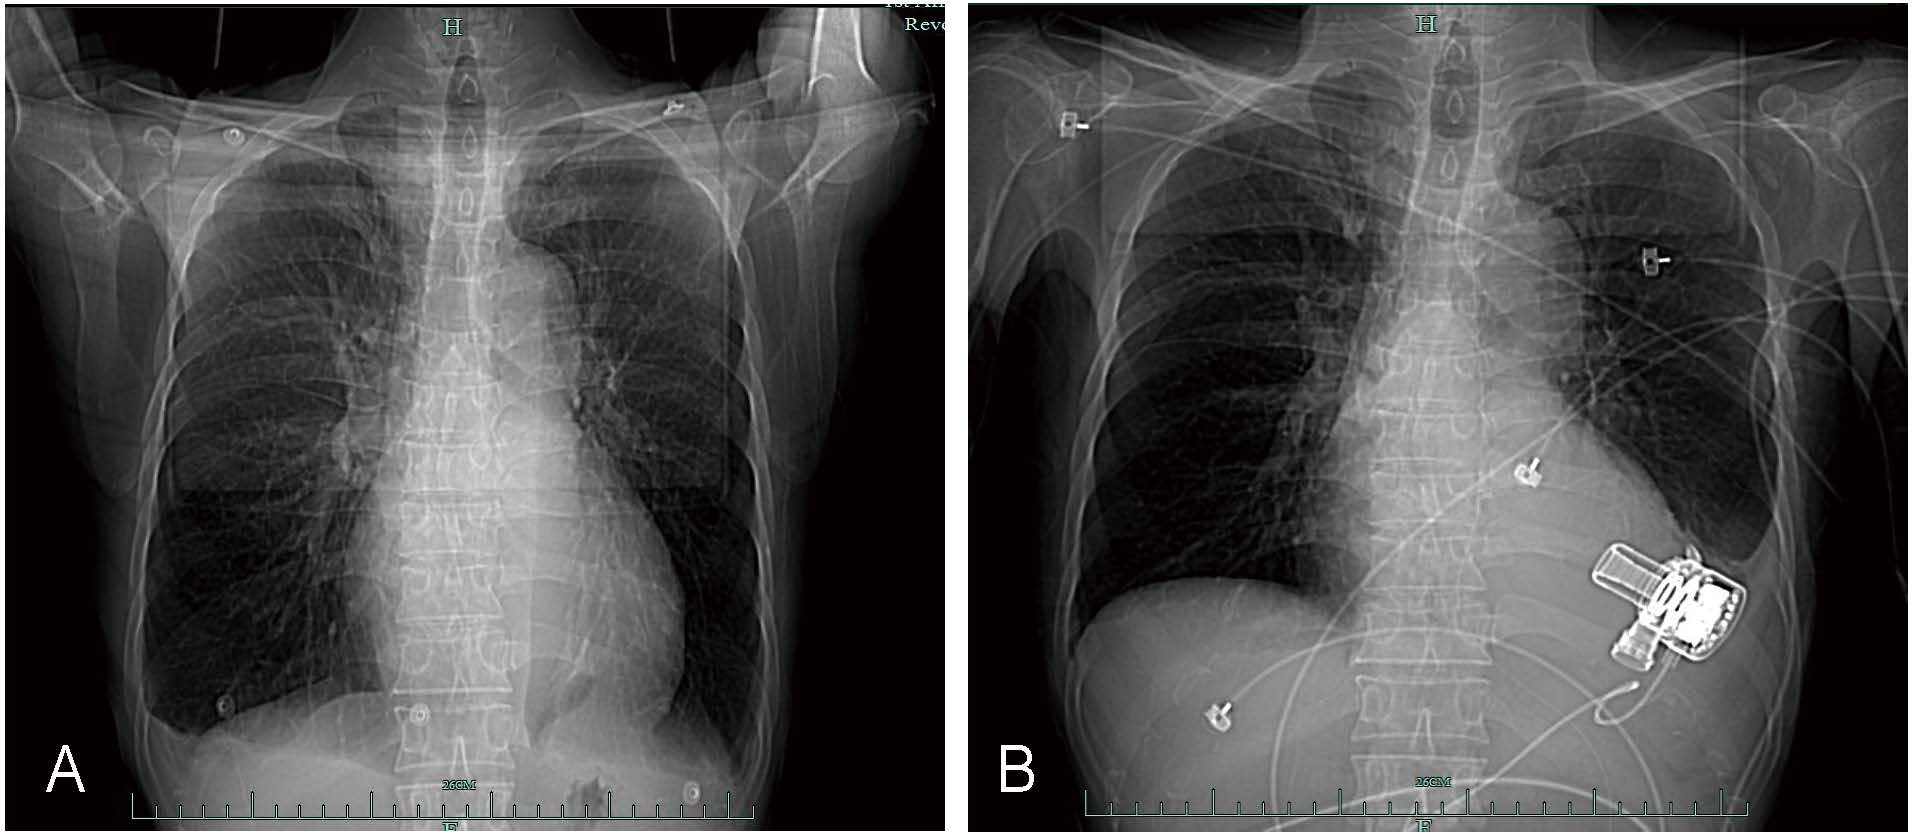

Electrocardiography revealed sinus tachycardia (115 beats/minute). Brain magnetic resonance imaging revealed no apparent abnormalities. Computed tomography (CT) of the lungs revealed signs of inflammation and emphysema (Fig. 1A). Pulmonary function tests revealed moderate to severe restrictive ventilatory impairment with moderate diffusion impairment. Echocardiography revealed mild mitral and tricuspid regurgitation, elevated pulmonary systolic pressure, significant enlargement of the left ventricle, diffuse hypokinesis of the left ventricular wall, and reduced left ventricular systolic function, with a left ventricular end-diastolic dimension of 63 mm and left ventricular ejection fraction (LVEF) of approximately 24% (Fig. 2A,B).

Fig. 1.

Chest computed tomography scans taken before and after surgery. (A) Before the operation. (B) After left ventricular assist device implantation.

The total operation time was 220 min, which included 98 min of cardiopulmonary bypass. Throughout the procedure, 350 mL of plasma, 1500 mL of crystalloid, and 100 mL of albumin were infused. Additionally, fibrinogen (0.5 g), prothrombin complex (300 units), and tranexamic acid (0.75 g) were administered. The estimated total blood loss was 500 mL, and the urine volume was 1300 mL. Echocardiography revealed that the left ventricular end-diastolic dimension was 48 mm, with an LVEF of 45%. The postoperative chest radiographs are shown in Fig. 1B.